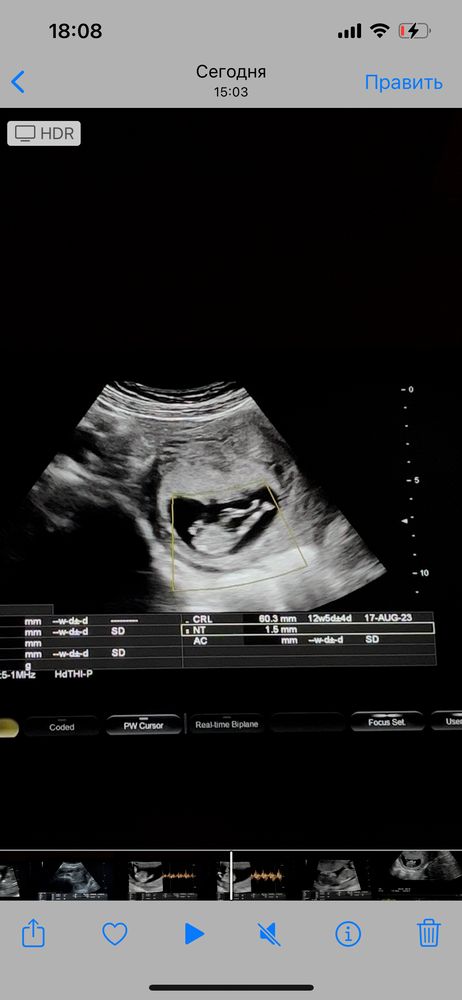

Всем привет 🤍 сегодня была на узи! 12,5недель, у меня есть 3 сына! ждём 4 малыша! Который 4,5 года к нам не приходил! сегодня снимала видео со скрининга, и думаю может можно что-то разглядеть?)) прилагаю скрины с видео , вид с боку и снизу 🤍 Благодарю за участия

Половой бугорок видно хорошо, он "торчит" практически параллельно телу, это же девчуля🥰

Похоже на девочку. Процентов на 80, как любят говорить врачи. Если на фото половой бугорок, то он параллельно позвоночнику